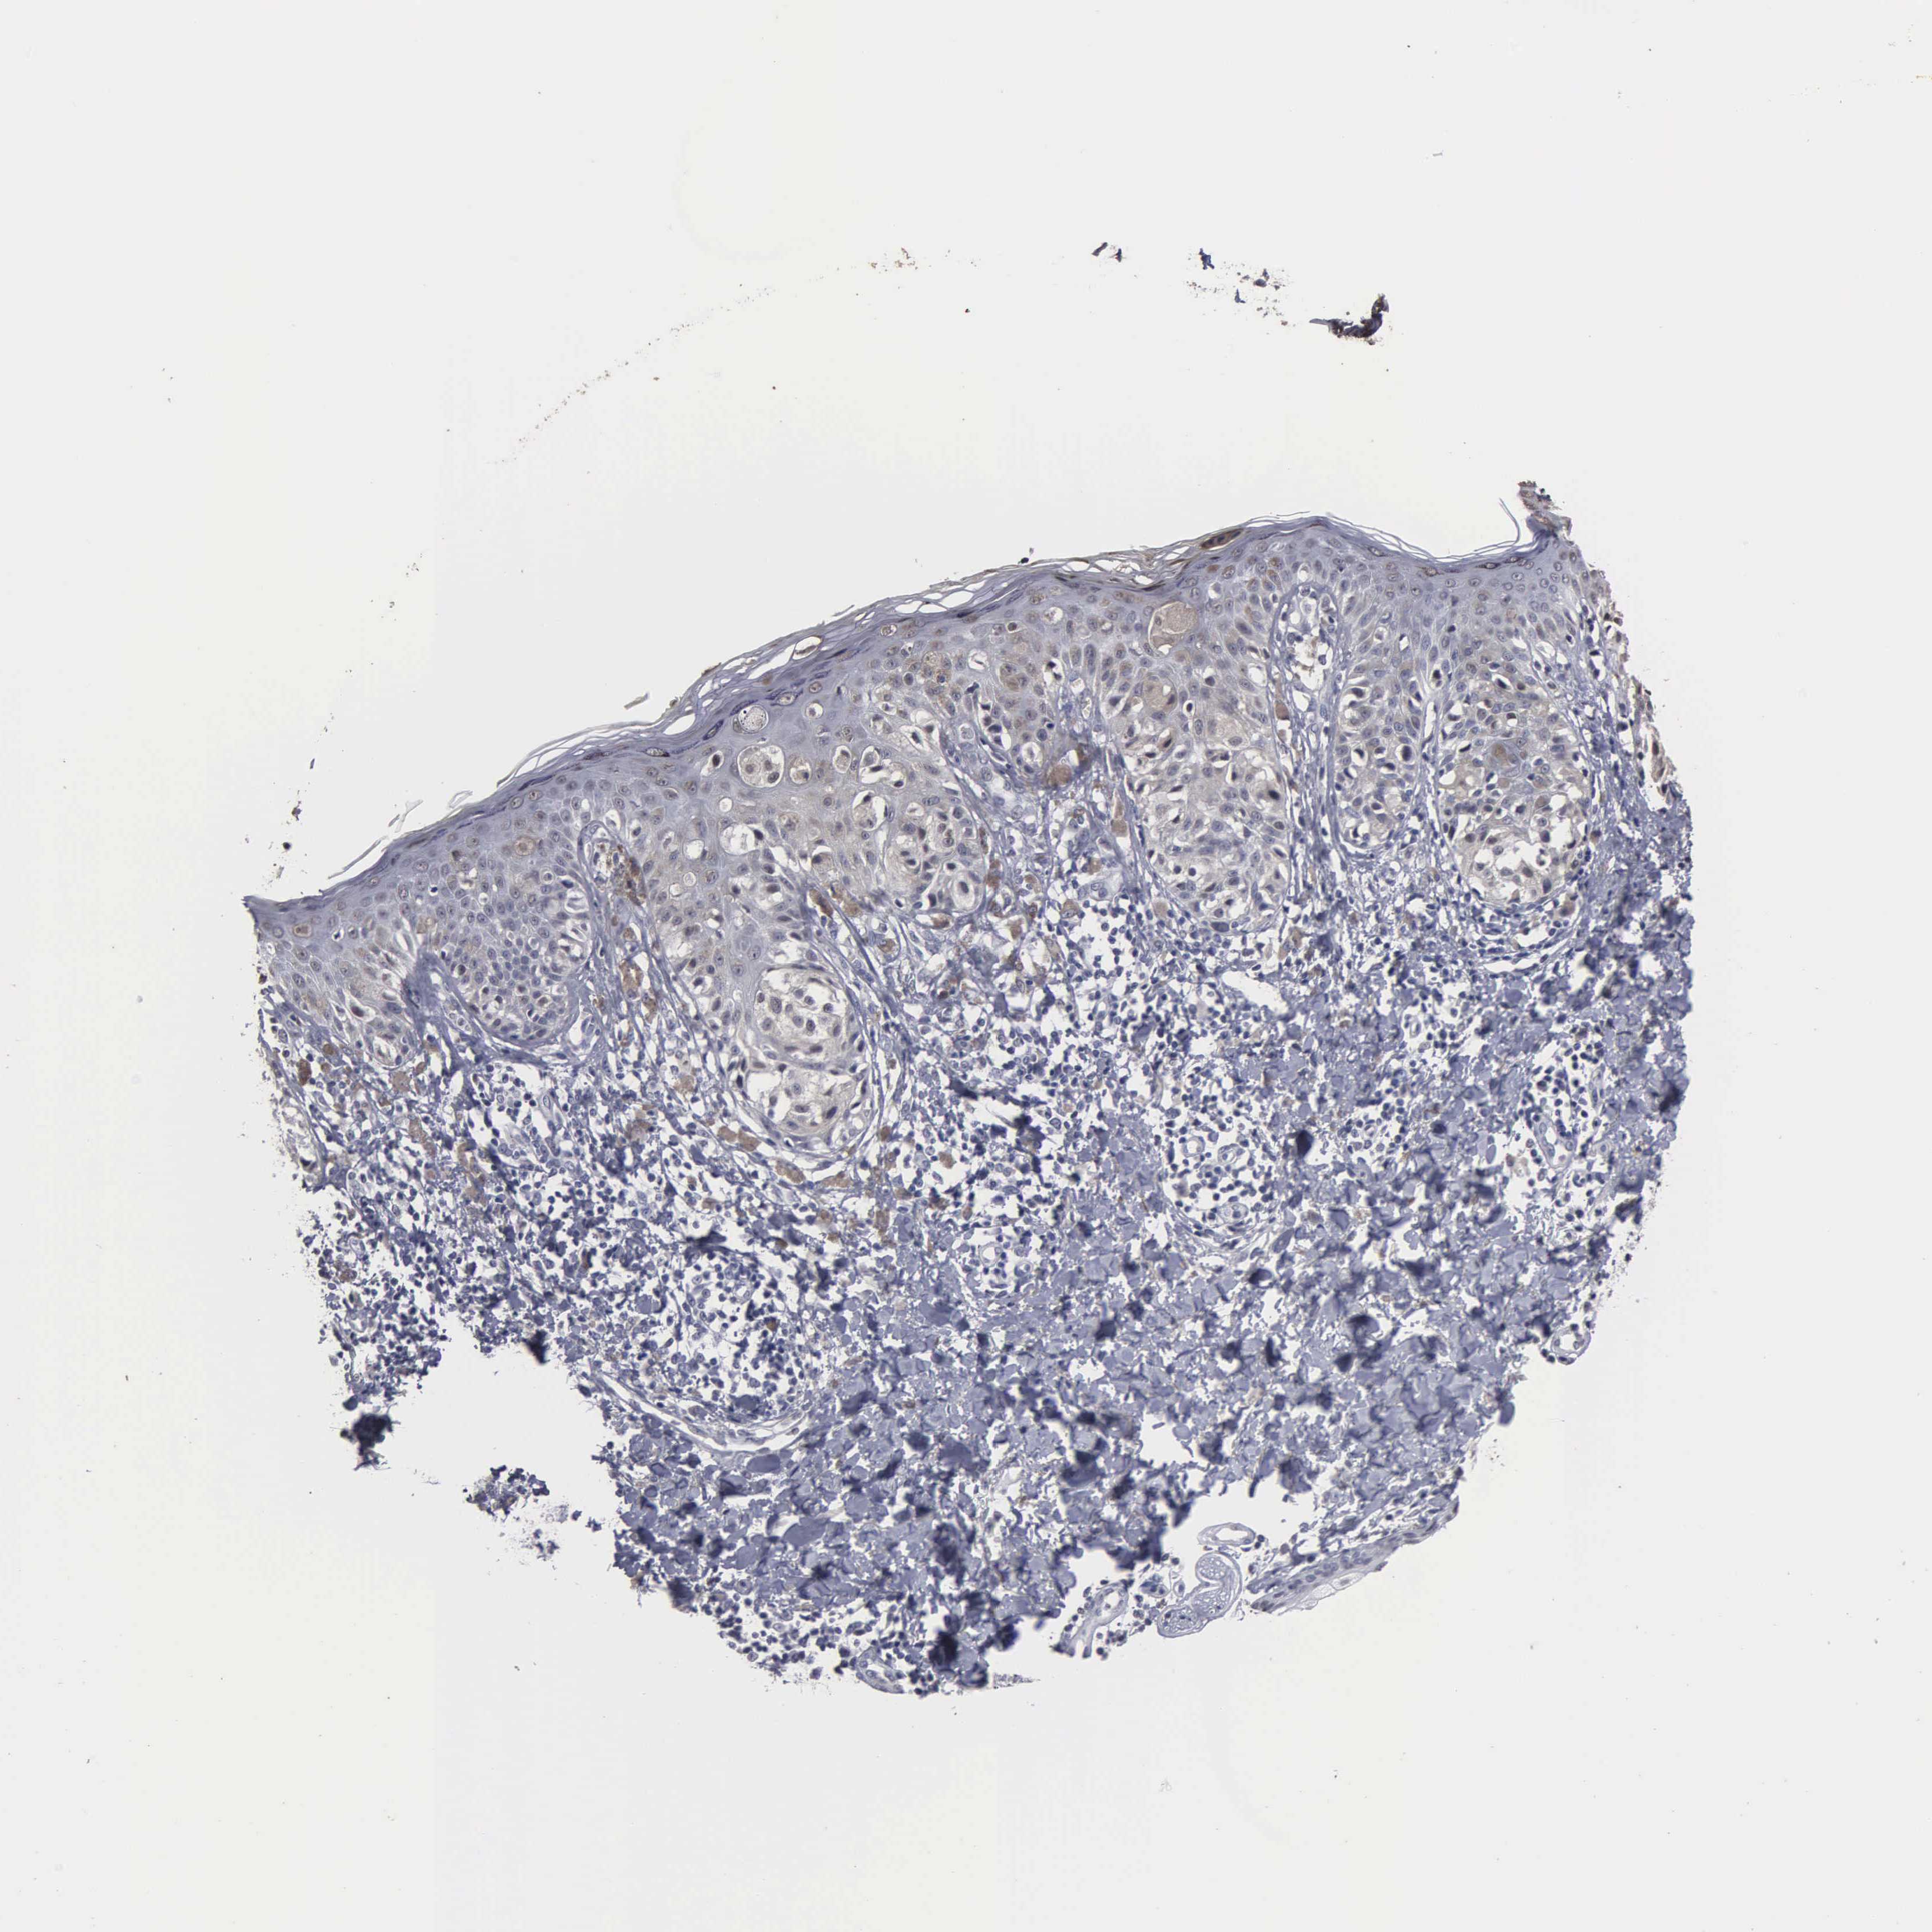

Antibody HPA000728

Antibody HPA076321

MELANOMA - Protein expressioni

A mouse-over function shows sample information and annotation data. Click on an image to view it in a full screen mode. Samples can be filtered based on level of antibody staining by selecting one or several of the following categories: high, medium, low and not detected. The assay and annotation is described here.

Antibody staining in the annotated cell types in the current human tissue is reported as not detected, low, medium, or high, based on conventional immunohistochemistry profiling in selected tissues. This score is based on the combination of the staining intensity and fraction of stained cells.

Each image is clickable and will lead to virtual microscopy that enables deeper exploration of all samples and also displays staining intensity scores, fraction scores and subcellular localization as well as patient and tissue information for each sample.

Malignant melanoma, NOS

Malignant melanoma, Metastatic site